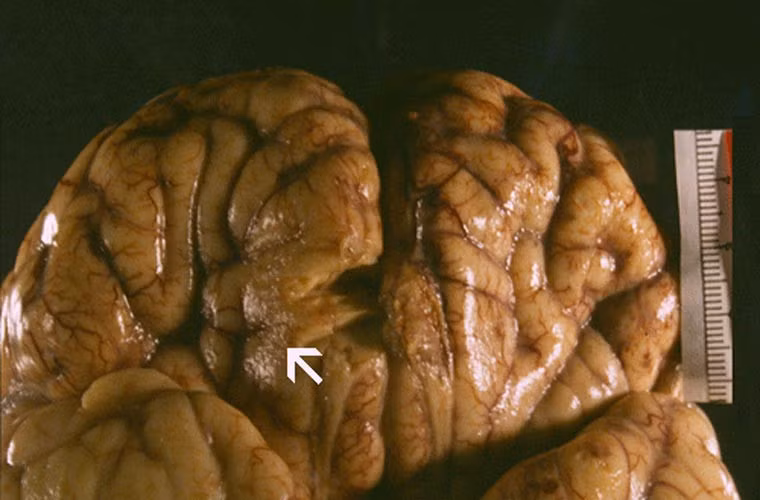

Khi xâm nhập vào cơ thể người, loại amip Naegleria fowleri sẽ sinh sôi, phát triển rất nhanh, sau đó di chuyển lên não người. Từ đây nó sẽ bắt đầu ăn các tế bào thần kinh gây nên chứng đau đầu khủng khiếp, bệnh nhân bị sốt, có ảo giác và thậm chí mất khả năng kiểm soát hành vi.

Ký sinh trùng Naegleria fowleri, còn được gọi là "amíp ăn não", có khả năng xâm nhập và tấn công vào hệ thống thần kinh của con người để ký sinh và gây bệnh. Nếu bị nhiễm ký sinh trùng này thì gần như đa số người bệnh đều bị tử vong.